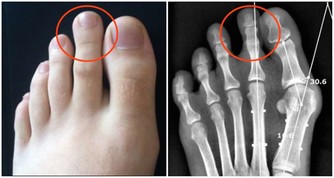

他提出「3不5時」快篩法,「更年期婦女3不5時腰酸背痛、每晚頻尿如廁超過3次,

每週3天睡眠不超過5小時,有任一症狀就該尋求婦產科醫師診治。」